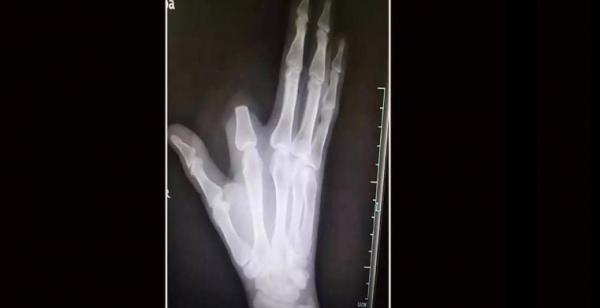

قطع إصبعه بسبب لدغة أفعى.. ثم اكتشف "المفاجأة الصاعقة"